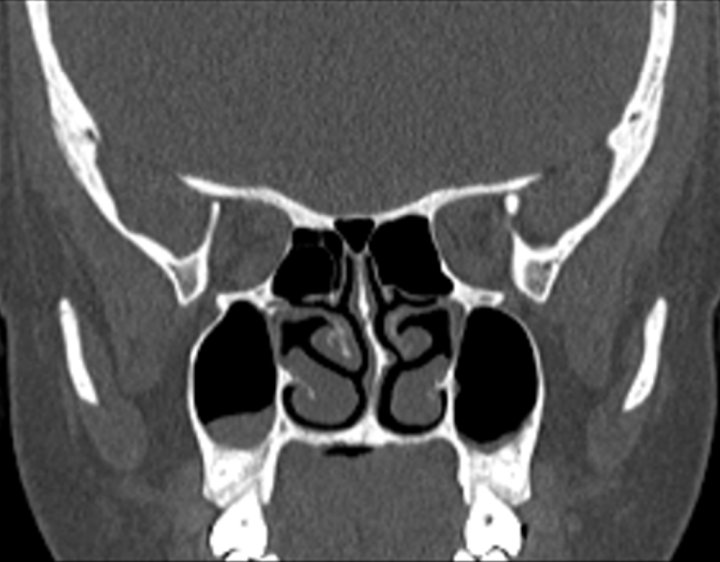

Click any image for labels.